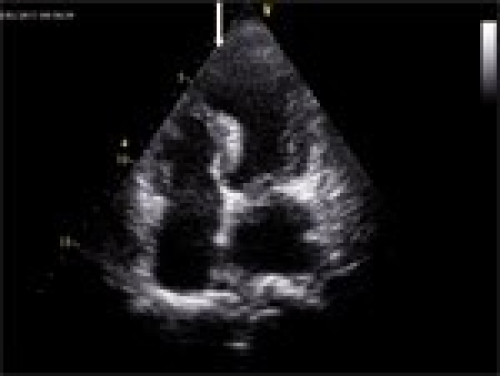

A severe complication after ST-segment elevation myocardial infarction (Part 1)